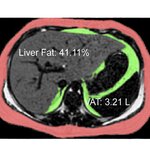

High Fructose Corn Syrup, Genes And Global Trade Policy: A “Perfect Storm” For Fatty Liver Disease In Hispanics

As the prevalence of obesity rises around the world, non-alcoholic fatty liver disease(NAFLD) is a growing concern, especially among the vulnerable Hispanic population.  Perhaps most alarming is that NAFLD, traditionally a disease of middle age, has become increasingly prevalent in childhood, where studies show that ~38% of obese Hispanic children and adolescents have liver fat levels in the range of clinically diagnosed NAFLD. NAFLD is the most common cause of fatty liver disease in the U.S., serving as a precursor to non-alcoholic steatohepatitis, which can lead to cirrhosis,…